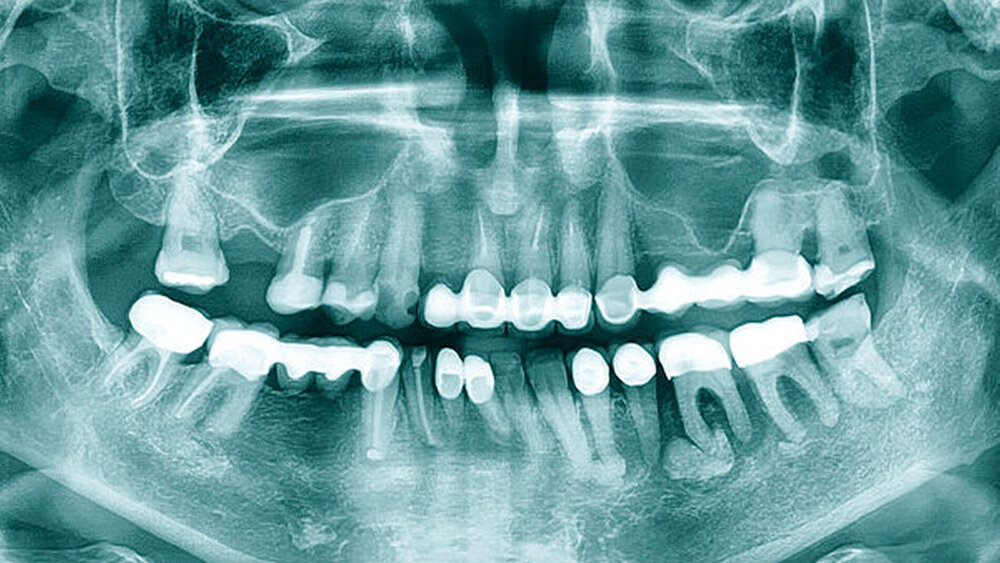

Die 56-jährige Patientin wollte vor geplanter Bisphosphonat-Therapie bei metastasiertem Mammakarzinom eine ausführliche zahnärztliche Befunderhebung und eine eventuell notwendige Fokussanierung durchführen lassen. Das ossär und hepatisch metastasierte Mammakarzinom entsprechend der TNM-Klassifikation pT2, pN1a (2/3 sn), G2, L0, V0, R0 (Erstdiagnose 2014) sollte nach Chemotherapie (2014) und lokaler Radiatio der Mamma (2015) nun auch mit Bisphosphonaten (Pamidronat, intravenös, alle vier Wochen) behandelt werden. In der beim Hauszahnarzt angefertigten Panoramaschichtaufnahme waren drei klar abgrenzbare Verschattungen mit umgebender Aufhellung im Bereich der Wurzelspitzen der Zähne 34, 36 und 37 zu erkennen. Zudem zeigte sich auch in regio 38 eine periapikale Osteolyse ohne zentrale Verschattung. Die betroffenen Zähne ließen sich – durch den vorhandenen parodontalen Spalt – klar von der jeweiligen Raumforderung abgrenzen (Abbildung 1). Voraufnahmen zum Vergleich lagen nicht vor.

Zur Einschätzung der Befundausdehnung wurde eine Computertomografie des Unter- und Oberkiefers angefertigt (Abbildung 2). Hier zeigten sich drei mehrsklerosierte Läsionen apikal in regio 34, 36 und 37 mit umgebenden Osteolysen. Die Wurzeln der Zähne ließen sich auch in der Schnittbildgebung vollständig von den sklerotischen Läsionen abgrenzen.

Radiologisch zeigen sich Fernmetastasen des Mammakarzinoms oft osteoblastisch, wie im vorliegendem Fall, als eine Verschattung mit umgebender Lysezone ohne Kontakt zum Parodontalspalt der Zähne [Chappard et al., 2011]. Bei im Kiefer gelegenen Verschattungen mit umgebender Aufhellung kommen differenzialdiagnostisch auch ein Zementoblastom (Parodontalspalt nicht von der Verschattung abgrenzbar), ein Odontom (Konvolut aus zahnähnlichen Strukturen mit umgebender Aufhellung), ein Osteosarkom (hyperdense sklerotische Veränderung ohne klare Begrenzung) oder ein Chondrosarkom (unscharf begrenzte Aufhellung mit Wurzelresorption der betroffenen Zähne) infrage. Zeigt sich eine Verschattung ohne umgebende Aufhellung, muss differenzialdiagnostisch auch an Osteome, Exostosen, Zemento-ossäre Dysplasien (multiple, scharf begrenzte Aufhellungen mit Kontakt zur Zahnwurzel) oder auch an eine Osteomyelitis (unscharf begrenzte Aufhellung mit teilweise radioopaken nekrotischen Bereichen) gedacht werden.

Der Vergleich zu eventuell vorliegenden Voraufnahmen kann die Abgrenzung zu stationären Prozessen wie stabilen Odontomen gegen Prozesse mit Progress erleichtern. Zusätzlich kann die Anamnese einen Hinweis auf die Genese eines Befunds geben. Die in diesem Fall bekannte Malignom-Anamnese der Patientin in Zusammenschau mit dem Befund der Panoramaschichtaufnahme und der Hypästhesie des N. alveolaris inferior (positives Vincent-Symptom) sind verdächtig für das Vorliegen eines pathologischen Prozesses mit Progress-Verhalten. In solchen Fällen ist die Dignitätssicherung der Läsion im Unterkieferknochen somit dringend empfohlen.